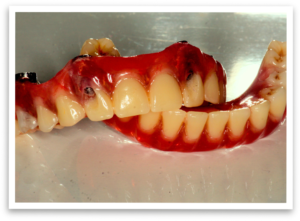

After a thorough examination and discussion, we planned the procedure.  A key aspect was the fabrication of an immediate denture in our in-house lab, ensuring Mr. B wouldn’t be without teeth for a single day.  We scheduled the procedure and eagerly awaited his new smile.

The day of the procedure arrived. Our team strategically placed four implants each in Mr. B’s upper and lower jaw (maxilla and mandible).  The immediate denture was then securely fixed onto the implants, immediately providing him with a functional and aesthetically pleasing smile.

Three months later,  we switched from the provisional denture to a permanent set of hybrid dentures, offering even greater comfort and durability. Mr. B now faces the world with renewed confidence.